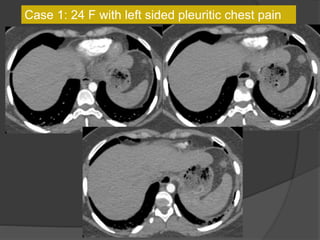

Case 1: 24 F with left sided pleuritic chest pain

CT 5 years ago

Diagnosis?

CT 5 years agoCurrent CT

Case 1 Diagnosis: Infarcted splenule

Infarcted splenule

 Accessory spleen (splenule ) : failure of fusion of the splenic

anlage, seen in up to 30% of autopsies

 Occur on vascular pedicles and thus at risk for torsion

 Differentiate from polysplenia and splenosis. Identify an intact

spleen, no other splenic foci and normal situs

 Recognize this entity as a cause of abdominal pain that can be

managed non-surgically

Case 14: 24 F with left sided pleuritic chest pain

Case 14 Diagnosis: Infarcted splenule